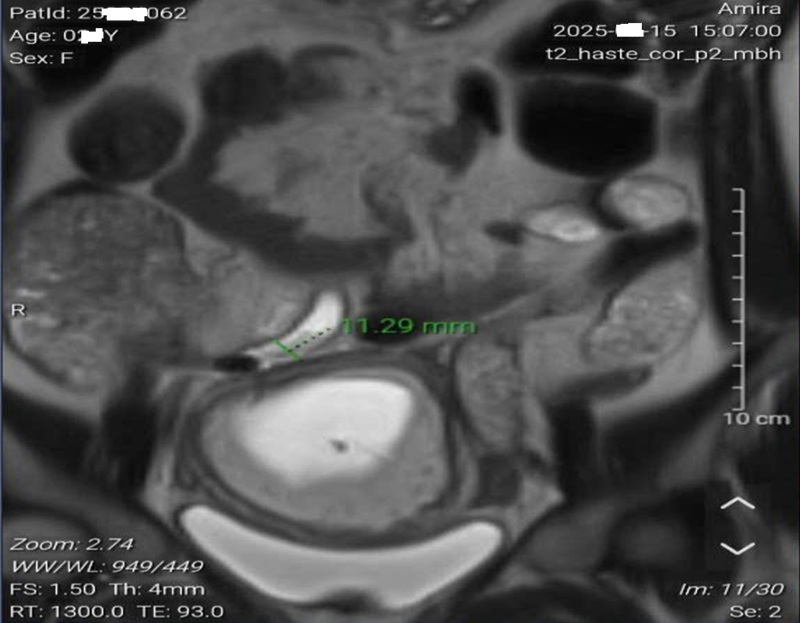

Kết quả chụp cộng hưởng từ (MRI) ổ bụng trước mổ khẳng định chẩn đoán của MEDLATEC Gò Vấp là chính xác. MRI ghi nhận ruột thừa vùng hố chậu phải tăng khẩu kính đến 12 mm, thành dày, phù nề, trong lòng chứa dịch, thâm nhiễm mô mỡ xung quanh và có sỏi phân tại gốc ruột thừa, kích thước 12 × 7 mm – hình ảnh điển hình của viêm ruột thừa cấp ở thai phụ.

Hình ảnh chụp cộng hưởng từ cho thấy có sỏi phân tại gốc ruột thừa